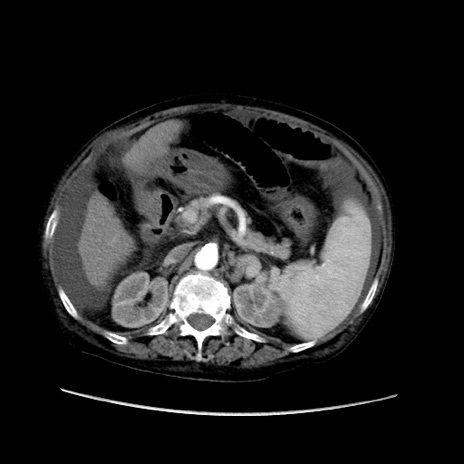

症例31(横断像)

【症例】80歳代 女性

【主訴】腹部膨満感

【現病歴】他院にて肝硬変にてフォロー中。1週間前から便秘、腹部膨満感、臍部腫瘤あり受診となる。

【既往歴】肝硬変

【身体所見】腹部膨隆あり、皮膚変化なし、疼痛なし。

【データ】WBC 4600、CRP 0.25